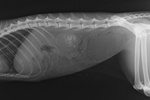

Dogs have long been called Man’s Best Friend, providing both companionship and work to their human owners. But VetCompass™ is now harnessing the power of Big Data Analyses from anonymised veterinary clinical records to take this friendship with dogs to a whole new level. Information from first-opinion veterinary data on millions of dogs now offers possibilities for huge advances in our understanding of many common human diseases.

Humans have experienced large increases in average lifespan over the last 150 years but this often means spending more years of later life with multiple chronic diseases. The closely entwined lives of companion dogs with their owners have suggested the dog as a powerful research model to better understand the genetic and environmental determinants of health in humans. But the shorter livespans of dogs mean that lifetime studies can be accomplished in roughly one-seventh of the time than what would be needed for a similar study in humans.

A ground-breaking new study involving the VetCompass™ Programme at the RVC reports that many chronic conditions that are both common and also commonly occur together in human populations (e.g. obesity, arthritis, hypothyroidism and diabetes mellitus) show very similar occurrence patterns in companion dogs. The effects of age on disease risk was also very similar between humans and dogs especially for neoplastic, congenital and metabolic causes of death.